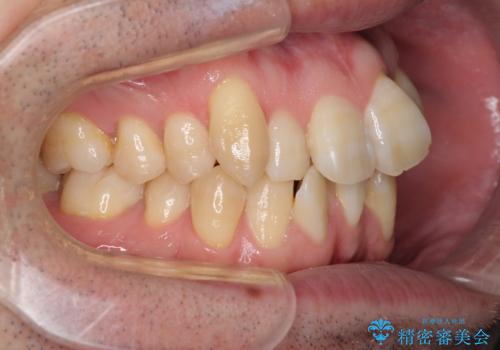

- 前歯のデコボコを気にして来院された患者様です。

叢生の解消とともに、前方に張り出した上顎前歯を引っ込めることを目的とし、上下左右の第一小臼歯4歯を抜歯をしてワイヤー矯正により治療することとしました。